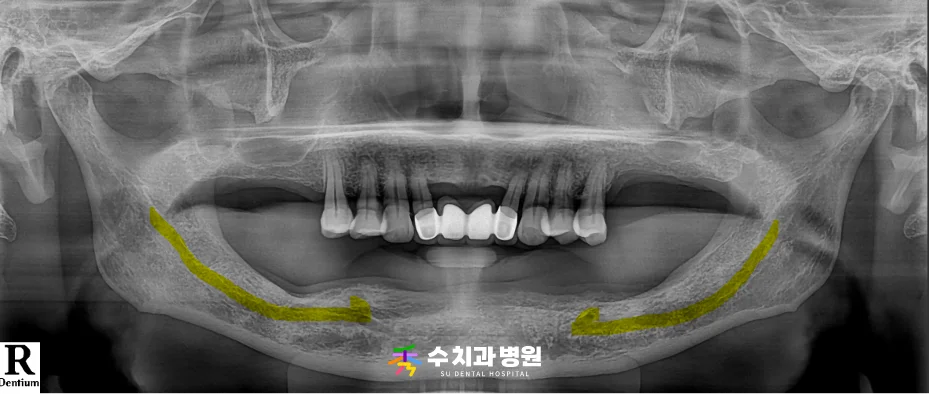

⏱️ 치료 후 경과

치료를 성공적으로 마무리한 후,

정기검진을 통해 방사선 사진을 촬영하며

임플란트 주위 잇몸뼈 상태를 점검했습니다.

[📸 치료 후 엑스레이] (촬영일: 2025년 5월)